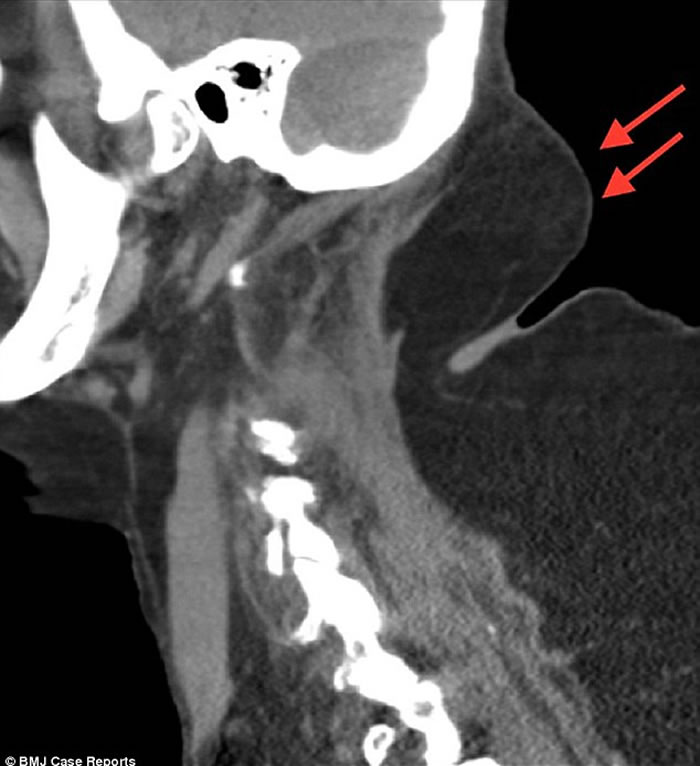

该名六旬妇人背部隆起(箭嘴示),犹如长有驼峰。

(神秘的地球报道)英国一名饮酒长达40年的64岁妇人,因长时间酗酒,导致背部隆起,长出一个类似驼峰的物体,于是到医院求医。医生看到妇人的颈部及手臂同样有囊肿后,到网上查证,发现她患上罕见的马德龙病(Madelung disease)。

根据《英国医学期刊》披露,该名妇人当日到来求诊时,意识混乱、无法告知时间,双手双脚亦无力。医生其后发现病人的上半身遍布囊肿,经血液测试后,确认她患上酮酸中毒。酮酸中毒一般见于患上一型糖尿病的人士,情况罕见并可致命。

现时医学界亦不清楚酗酒如何导致患上马德龙病,但指非饮酒人士或会因DNA的转变,也有机会患上该病。经过与医生讨论后,该名妇人决定停止饮酒,但不愿意接受手术。